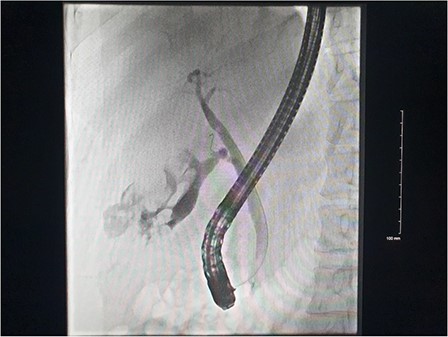

Right common femoral artery access was achieved, followed by Mickelson catheter access to celiac axis. Digital subtraction angiography (DSA) demonstrated active haemorrhage arising from the cystic artery (Fig. 2). A Renegade HiFlow microcatheter (Boston Scientific) was advanced into the cystic artery arising from the right hepatic artery. A repeat DSA in this position demonstrated multiple points of active haemorrhage around the gallbladder with two main branches arising from a central trunk. A single 3 × 3.3 mm Vortx coil (Boston Scientific) was deployed into the proximal cystic artery. A repeat DSA through the microcatheter in the right hepatic artery demonstrated the cessation of flow in the cystic artery and no further active haemorrhage (Fig. 2).

DSA images demonstrating active haemorrhage from the cystic artery and subsequent coil embolization with cessation haemorrhage.